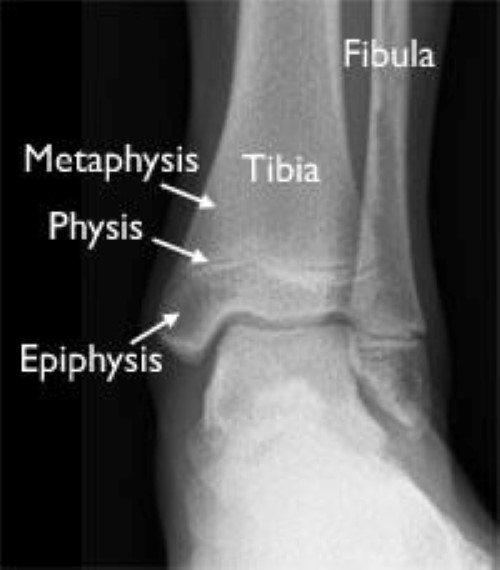

growth plates in ankle

This X-ray of a child's ankle taken from the front clearly shows the growth plates of the tibia and fibula (red arrows).